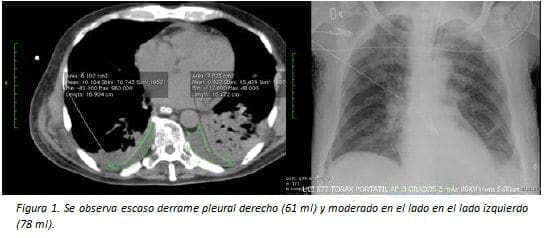

La cantidad depende del área en cm2 obtenida en escanografía de tórax en corte axial en el sitio donde era más abundante. Esta medida del área fue convertida en mililitros utilizando la fórmula ml = (cm2 x 100) x 0,1.

A su vez fue determinado como escaso si es <75 ml, moderado entre 75 y 350 ml y abundante si es mayor de 350 ml (figuras 1-5).